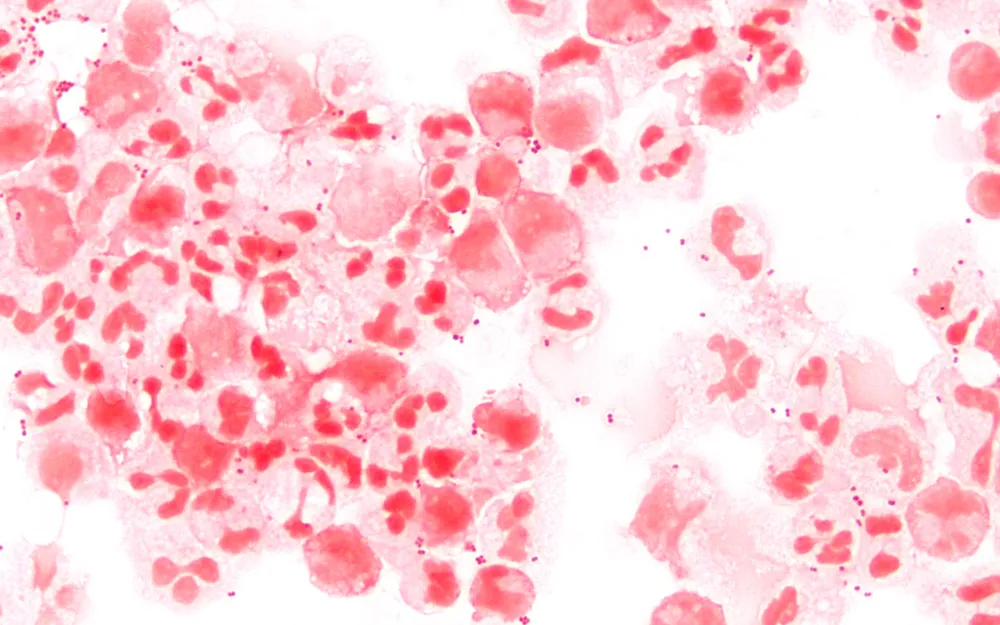

Neisseria meningitidis, a bactéria que causa a meningite meningocócica. — Foto: Wikimedia